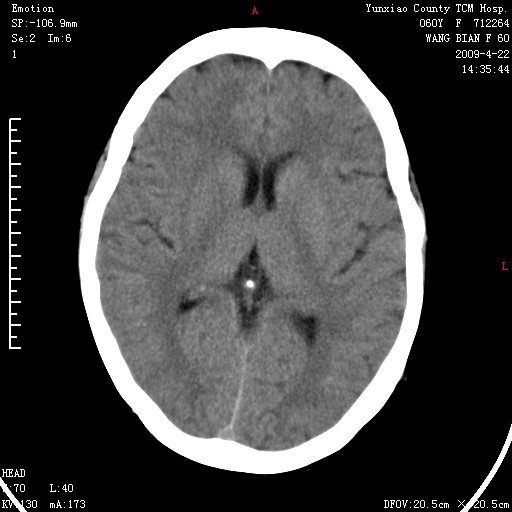

1、头颅未见明显异常。

2、左肾囊肿。

1、头颅未见明显异常。2、左肾囊肿可能。建议增强

1、枕骨蛛网膜粒压迹。2、左肾囊肿可能。建议增强

头颅未见明显异常。左肾囊肿。

1)枕骨蛛网膜粒压迹。2)左肾囊肿可能。